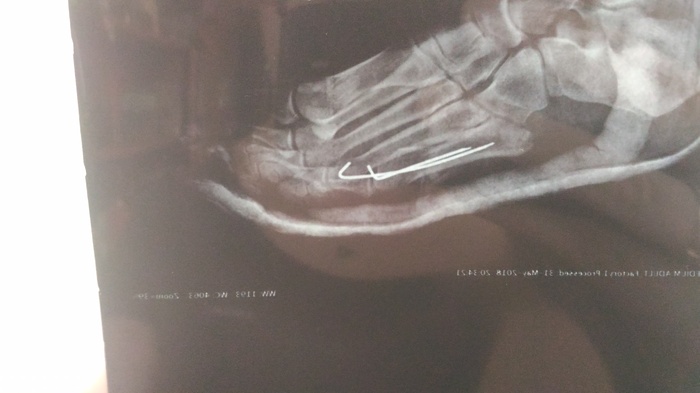

Отсидев в очереди два часа (что еще не так много на самом деле), мы зашли в кабинет к врачу, не дав и слова сказать он начал на повышенных тонах отчитывать брата рассуждая, а стоит ли вобще брать его на прием. Никаких оправданий он выслушивать не захотел, говорил все время на повышенных тонах брат вышел из кабинета, так как он разозлился от такого обращения и сказал, что вобще ни к какому врачу не пойдет. Пока суть да дело, я договорилась что нас примет дежурный врач. На приеме выяснилось, что у брата произошло смещение отломка

Сказали что такое случается и предложили съездить во Вредена на консультацию о том, что делать дальше.

Вот собственно вчера были на консультации, доктор увидев снимки спросил кто сотворил сей ужас (про спицы). Сказал, что при таких переломах спицы на закрытую не ставят, нужно обязательно делать операцию, ставить либо пластинку либо шуруп, в зависимости от обстоятельств. А так одна спица немного кость держит, а другая вобще ничего не фиксирует. Операция платная и дорогая соответственно, за деньги мы к сожалению не можем себе ее позволить. У подруги (она врач) узнавала - бесплатно можно сделать, но тут 50 на 50, как она сказала скорее всего соберут плохо. Можно по направлению делать во Вредена и оплатить палату, что бы не так долго очередь ждать. Можно вообще ничего не делать, но тогда сказали что возможно будут проблемы при ходьбе, так как кость опорная, а в последствии могут быть проблемы с позвоночником.